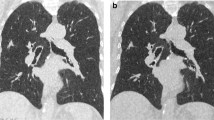

Both types of sequential scans resulted in a lower radiation dose, lower number of acquired slices and longer scan time, as shown in Table 2. Acquisition scan time was ≤33 s in all cases. The sequential scan at 50 mAs resulted in a median effective dose of 0.09, comparable to that of a digital chest X-ray [22]. Figure 2 illustrates axial, coronal and 3D reconstructions of the three acquisition protocols in a representative animal.

Scanning protocols. Axial (upper panels), coronal (middle panels) and 3D reconstructions (lower panels) of the three acquisition protocols in a representative animal. Colors in the 3D reconstruction represent clusters of lung tissue: hyper-aerated (blue), normally aerated (green), poorly aerated (yellow), non-aerated (red)